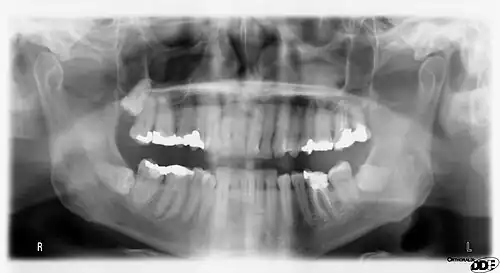

Panoramic radiograph

A dental panoramic radiograph, showing the maxilla and mandible, all the teeth including the "wisdom teeth," the frontal and maxillary sinuses, the nasal cavity and the temporomandibular joint and other near by head and neck anatomy. | |

A panoramic radiograph is a panoramic scanning dental X-ray of the upper and lower jaw. It shows a two-dimensional view of a half-circle from ear to ear. Panoramic radiography is a form of focal plane tomography; thus, images of multiple planes are taken to make up the composite panoramic image, where the maxilla and mandible are in the focal trough and the structures that are superficial and deep to the trough are blurred.

Orthopantomograms (OPTs) are used by health care professionals to provide information on:

- Impacted wisdom teeth diagnosis and treatment planning - the most common use is to determine the status of wisdom teeth and trauma to the jaws.